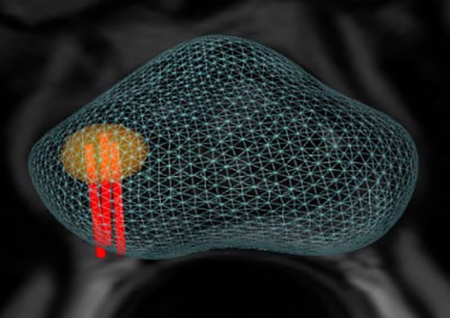

Με την νέα μέθοδο επιτυγχάνεται με απόλυτη ακρίβεια η λήψη υλικού βιοψίας αποκλειστικά και μόνο, από τα προς διερεύνηση εντοπισμένα ύποπτα σημεία, που έχουν ήδη αναδειχθεί στην προηγηθείσα πολυπαραμετρική μαγνητική τομογραφία προστάτη.

- Την ελαστική συγχώνευση τρισδιάστατων εικόνων Υπερηχογραφήματος και Μαγνητικής Τομογραφίας σε πραγματικό χρόνο μέσω του λειτουργικού συστήματος εντοπισμού Organ-Based Tracking Fusion( OBT Fusion).

- Aπεικόνιση του προστάτη σε τρισδιάστατη μορφή.

- Λήψη βιοψίας σε εικονικό και πραγματικό χρόνο